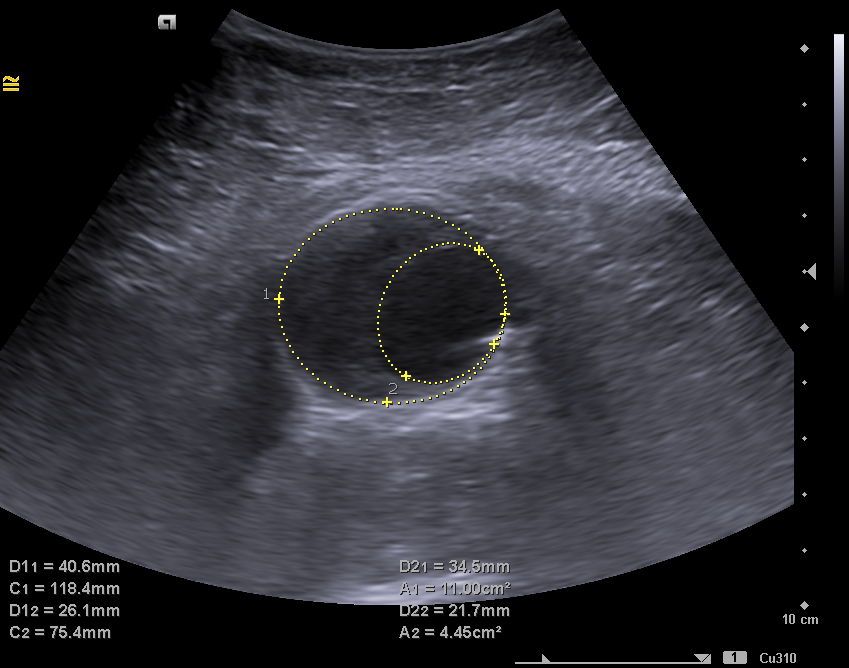

En la ecografía clínica se observa la aorta abdominal con calibre aumentado de tamaño (46 x 41 mm de diámetro), trombo mural interior y luz del vaso de 20 x 27 mm compatible con aneurisma de aorta abdominal fusiforme que se extiende hasta bifurcación aortoilíaca. Arterias ilíacas comunes sin datos de afectación.